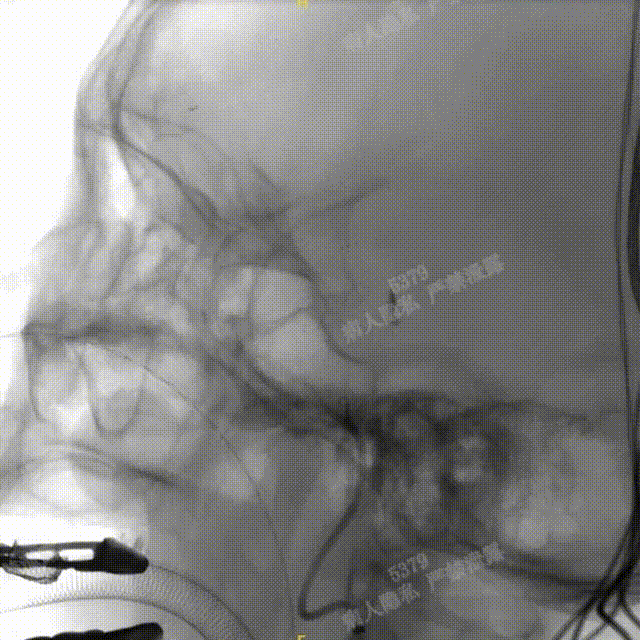

术中DSA造影:左侧颈内动脉正、侧位及3D造影,显示左侧颈内动脉后交通段动脉瘤。

术中DSA造影:右侧颈总动脉3D造影及右侧锁骨下正位造影。